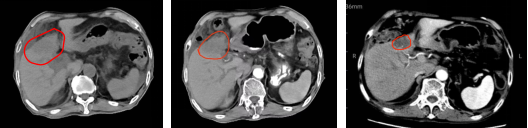

Case Presentation 2: Cholangiocarcinoma

An intrahepatic cholangiocarcinoma in liver segment S4 (47×35×37 mm) involved the gallbladder and hepatic portal, with left hepatic duct dilation. Pathology confirmed moderately differentiated adenocarcinoma, staged cT4N1M0 IIIB. The patient received carbon-ion radiotherapy (total dose PTV 68.4 Gy [RBE]/18 fractions) alongside targeted therapy (lusanutuzumab 200 mg every 3 weeks), achieving sustained remission in long-term follow-up.

(Pre-treatment)2025-04-23 (2 Weeks Post-treatment)2025-5-7 ( 4 Months Post-treatment)2025-09-26